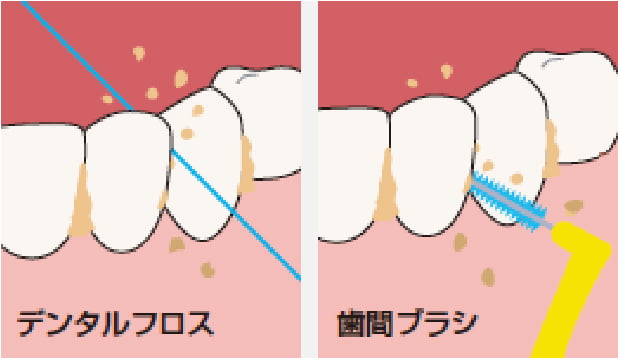

ブラッシング指導・スケーリング

歯周病の原因となる歯周病菌を取り除くため、ブラッシング指導スケーリング(表面の歯石の除去)を行います。歯周病治療の成否を決める重要な段階ですので、歯科医師と担当歯科衛生士が、時間をかけて丁寧に行います。

-

歯ブラシの他にもうひとつ

指導を受けて適切な方法や清掃用具を使いましょう。